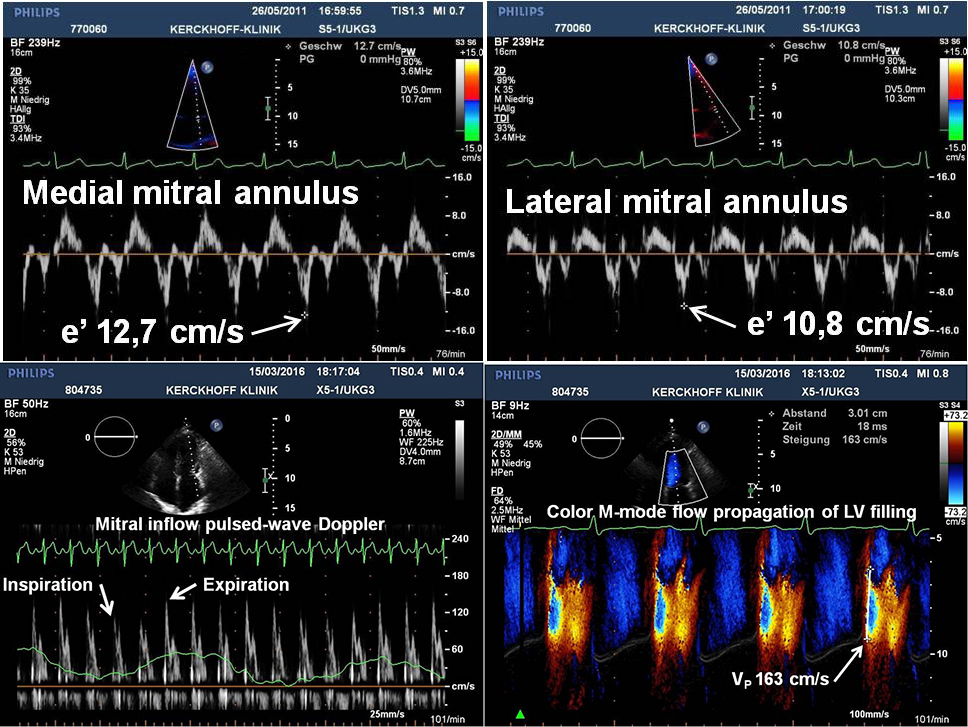

The Doppler images are suggestive of what cardiac pathology or condition?

Constrictive Pericarditis

Pericardial effusion

Dressler's syndrome

Acute pericarditis

Restrictive Cardiomyopathy

Pericarditis versus Restrictive Cardiomyopathy: Select all the following answers (multiple answers) that apply to the image:

Surrounds entire heart, impedes diastolic filling

Restrictive/ Infiltrated Cardiomyopathy

Large MV E, small A, with respiratory changes

Involves infiltrated myocardium, stiff ventricular walls, impedes diastolic filling

Large MV E, small A, without respiratory changes

Pericarditis verses Restrictive Cardiomyopathy: Select all the following answers (multiple answers) that apply to the image:

Explain 2 findings in these images that support the diagnosis of constrictive pericarditis.